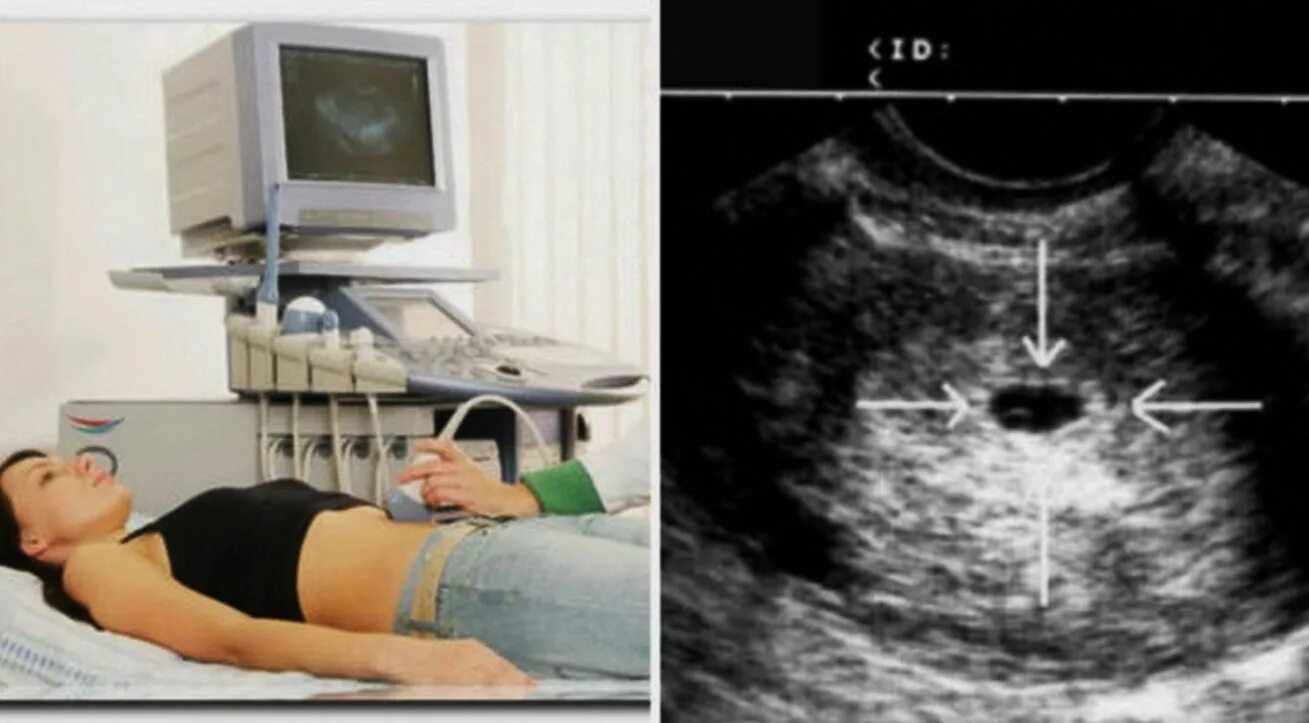

Как называется узи на ранних сроках